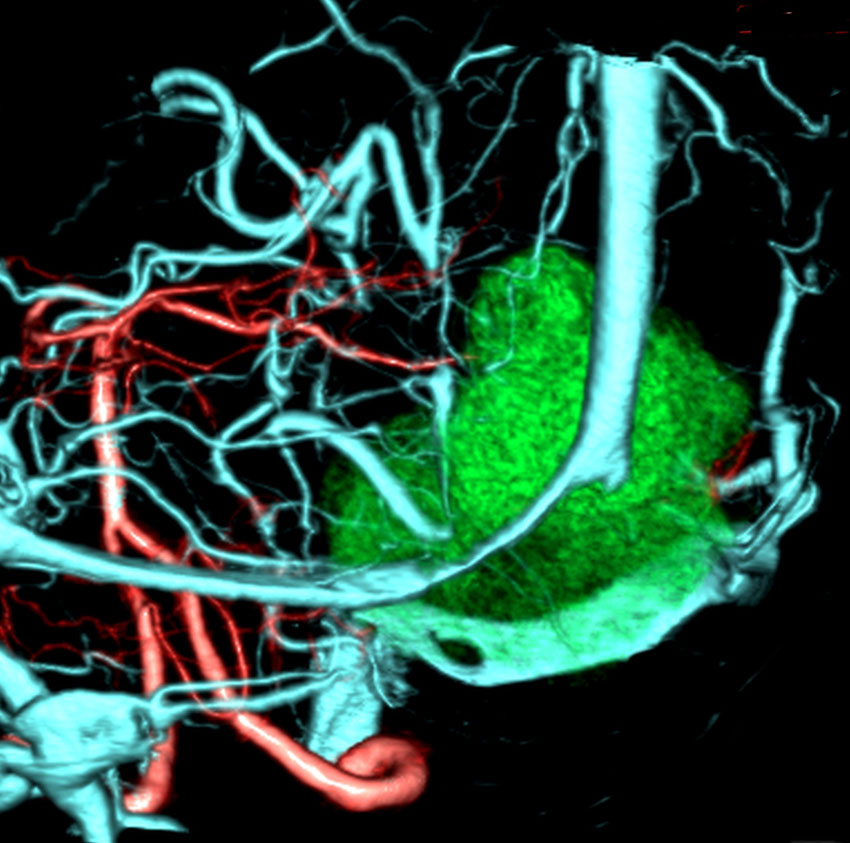

静脈洞交会 confluence に浸潤しているものです。直静脈洞は閉塞しています。右のMRIでは,ガドリニウム増強像が強弱まばらになっています。髄膜腫と診断したいのですが,ちょっと何かが違うというのがSFTです。硬膜や骨や脳に浸潤性格を有します。亜全摘出して術後に54グレイの放射線治療をしました。

5年後に小脳内に再発しました。全摘出したのですが,その後もあちこちに再発を繰り返しています。最初はグレード2でしたが,再発を繰り返すと増大速度が速くなり,再発までの期間が短くなり,多発性再発となってきます。